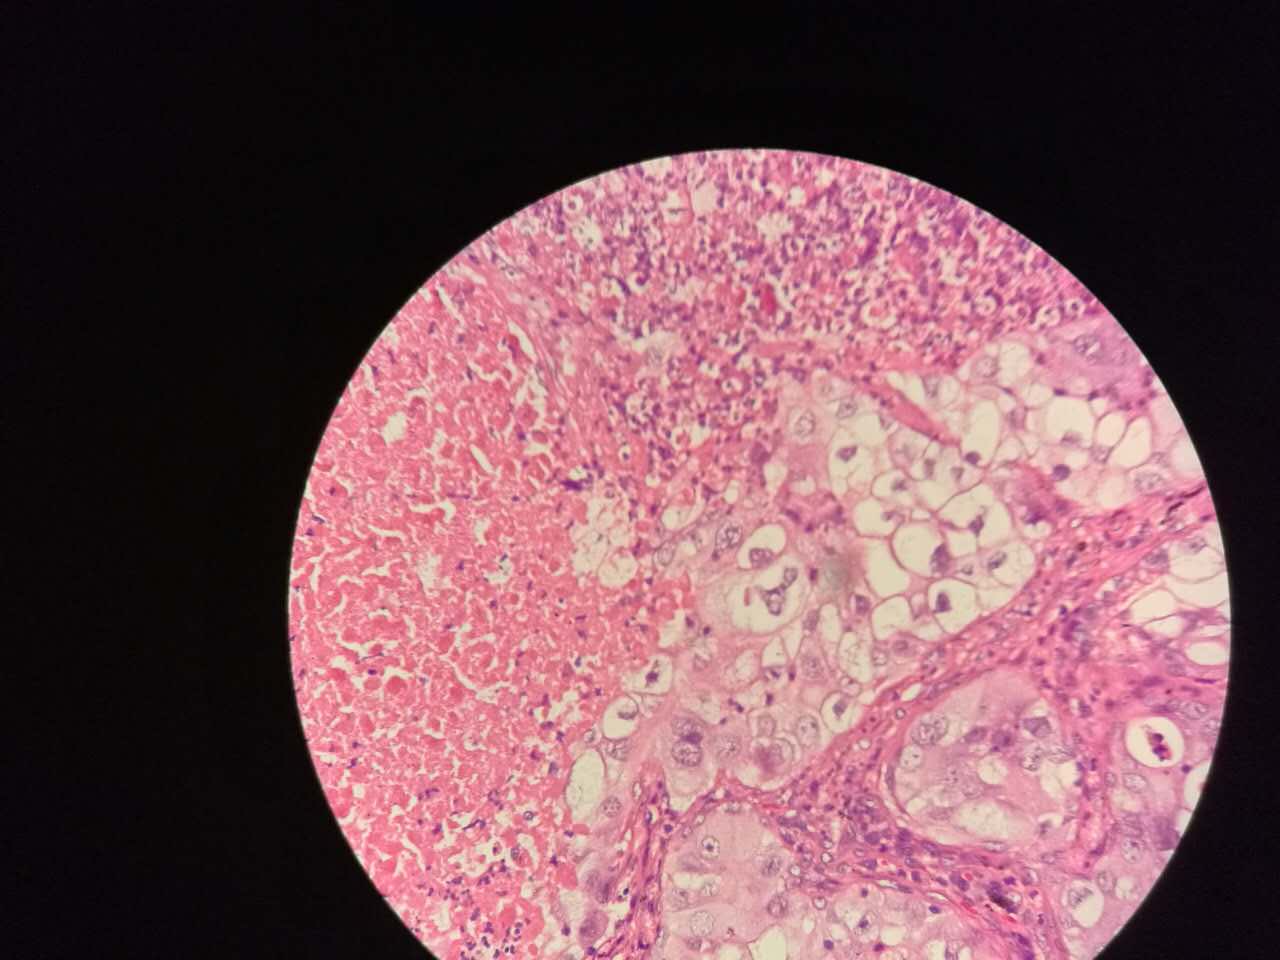

鳞癌生长,呈巢团状

巢团边界大多清楚

巢团可以很大,中央血供不足,就会坏死

中央红色的,有碎核

坏死也可以很大

较大的粉红区都是坏死,可以看出坏死是因为巢团大,中央坏死

坏死会有许多团,有些只有一毫米大小,所以,建议增强扫描时候保留肿瘤区的薄层,以看到更多坏死区

这个下面的软骨说明了是大气管,中央型

鳞癌长在支气管,很容易阻塞,截断

远侧可以阻塞性肺炎或阻塞性肺不张

左手边有一点鳞癌,右手边有正常肺泡组织,中间有坏死物,这是为什么呢?

坏死物质渗出。

一侧常有突起,也就是壁结节。

壁结节不必等到空洞形成才判断,有坏死区就可以在增强片上判断有无壁结节

这个中央那块也算是小型的壁结节,肿瘤组织突入坏死区。或者说,这块肿瘤组织没坏死。